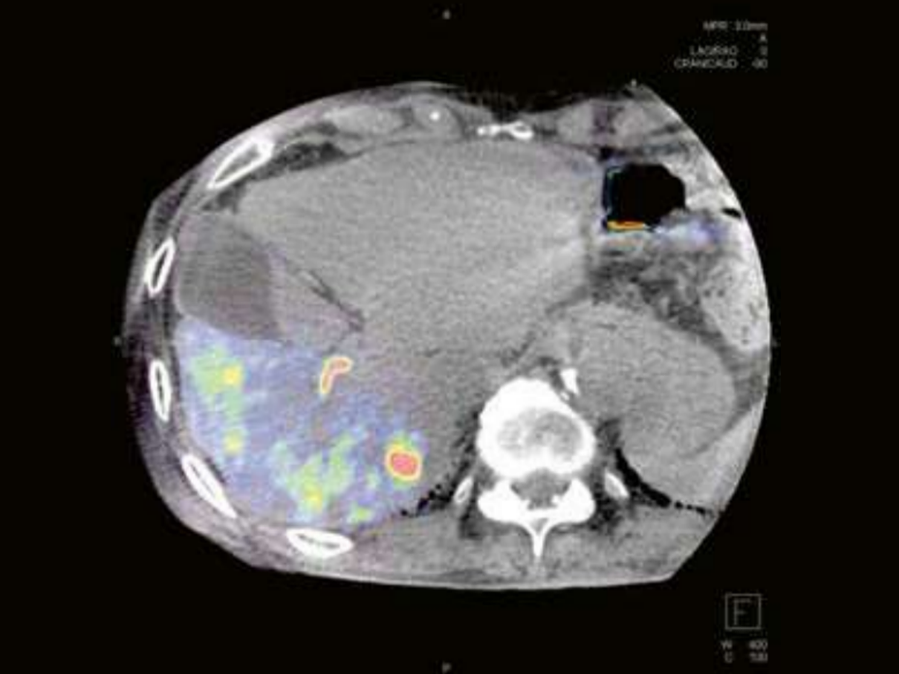

Blood volume map overlaid on native syngo DynaCT images provided by syngo DynaPBV Body.

Courtesy: Prof. Vogl, Dept. of Diagnostic and Interventional Radiology, University of Frankfurt, Germany

The software indicates the distribution of blood in lesions and surrounding tissue by means of color-coded cross-sectional blood volume maps. Based on this blood volume information, physicians can evaluate changes in perfusion caused by treatment or biological processes. It can be used to monitor response to treatment following repeated TACE and has the potential to identify potential non-responders directly intra-procedurally.